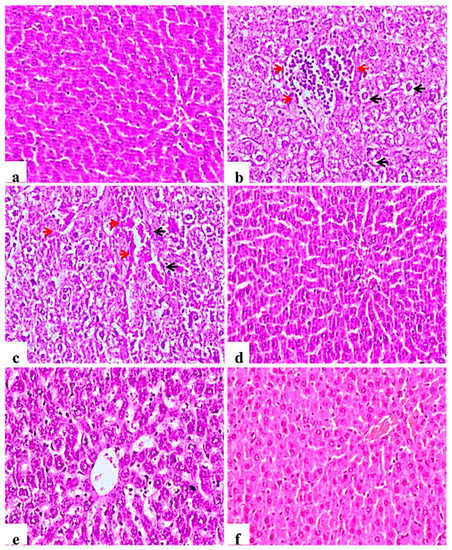

2.9.3. Liver